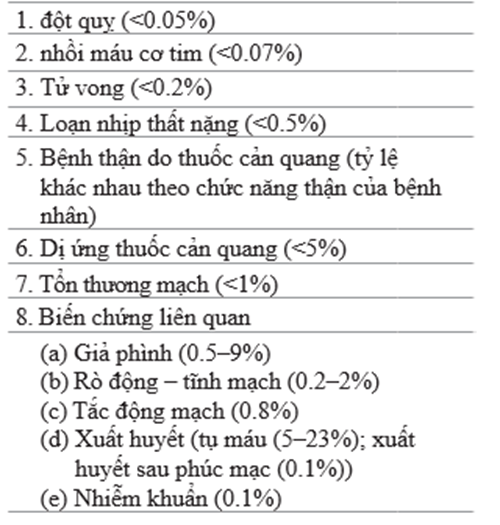

4. Đặt catheter tim tương đối an toàn. Tuy nhiên, có 1 số biến chứng có thể xảy ra và bệnh nhân cần được trao đổi kỹ về chúng trước khi tiến hành thủ thuật xâm lấn. các biến chứng chính [5, 6] được tóm tắt trong bảng Table 71.4.

Table 71.4 tỷ lệ biến chứng khi đặt thông tim